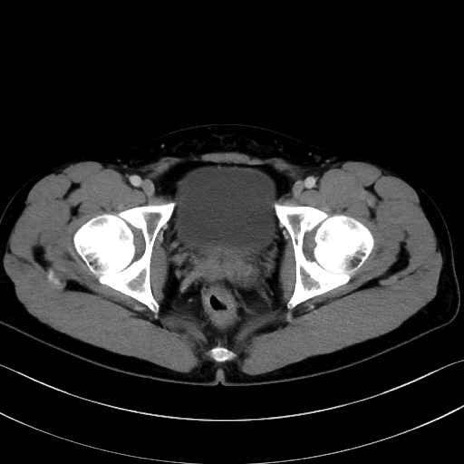

内閉鎖筋 (Obturator internus)

外閉鎖筋 (Obturator externus)